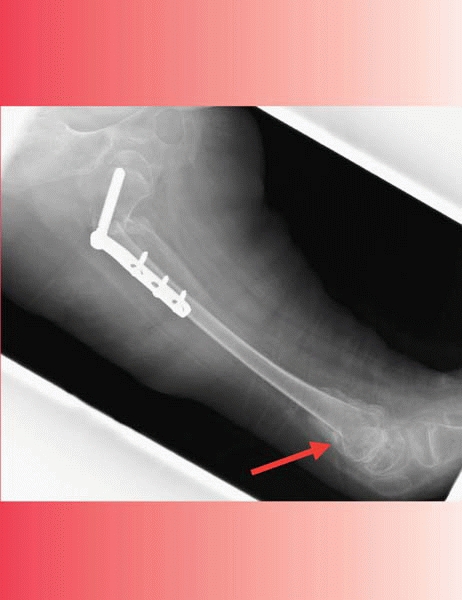

hip reconstruction. The fixation can cut out easily (Fig. 14-5).

![]() |

|

▪ FIGURE 14-3 Persistent adduction made worse with VDRO.

▪ FIGURE 14-4 Too much “DR” in a “VDRO?” Partial hip subluxation (A) was treated with a VDRO (B) and Dega pelvic osteotomy. (C)

Five years after healing and hardware removal, this AP radiograph shows a rotational abnormality that is difficult to interpret, and the hip has a severe fixed internal rotation contracture. (D) A CT scan shows 30 degrees of anteversion. Since this was felt to reflect primarily soft-tissue contracture, he had a lengthening for the adductor, gluteus minimus and medius, fascia lata, and anterior hip capsule. If there would have been any femoral retroversion, this would have had to be combined with a femoral derotation. (E) This followup CT scan obtained one year after the releases demonstrates a much improved relationship of the femoral head to the acetabulum. On examination, external rotation has been restored. (Courtesy of F. Miller, MD.) |

▪ FIGURE 14-5

Intertrochanteric fracture following blade plate fixation as part of a hip reconstruction. Low bone density, spasticity and aggressive postoperative therapy combine to increase fracture risk. Technique was an additional factor in this case: the blade plate was quite low in the neck. |